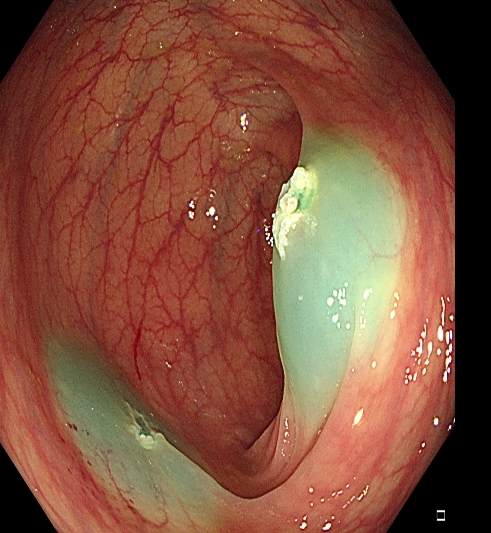

对于大型Ⅰp病变,除以上注意事项外,应采用热圈套方式切除,切除前应于蒂根部充分黏膜下注射(经内镜注射针将2~10 mLl万单位的肾上腺素+亚甲蓝+生理盐水混合液注射于黏膜下,边退针边注射),致使蒂部充分隆起,易于切除(图 3),切除过程中病变应避免接触肠壁,以免形成闭合回路,灼伤肠壁。

需要注意的是大型Ⅰp型息肉若蒂部较粗,则可能含粗大滋养血管,切除后极易出血。切除过程中可采用凝-切-凝的方式,减少出血风险。部分较大息肉,可采取分块切除方式,降低操作难度,但此法不利于病理评估。